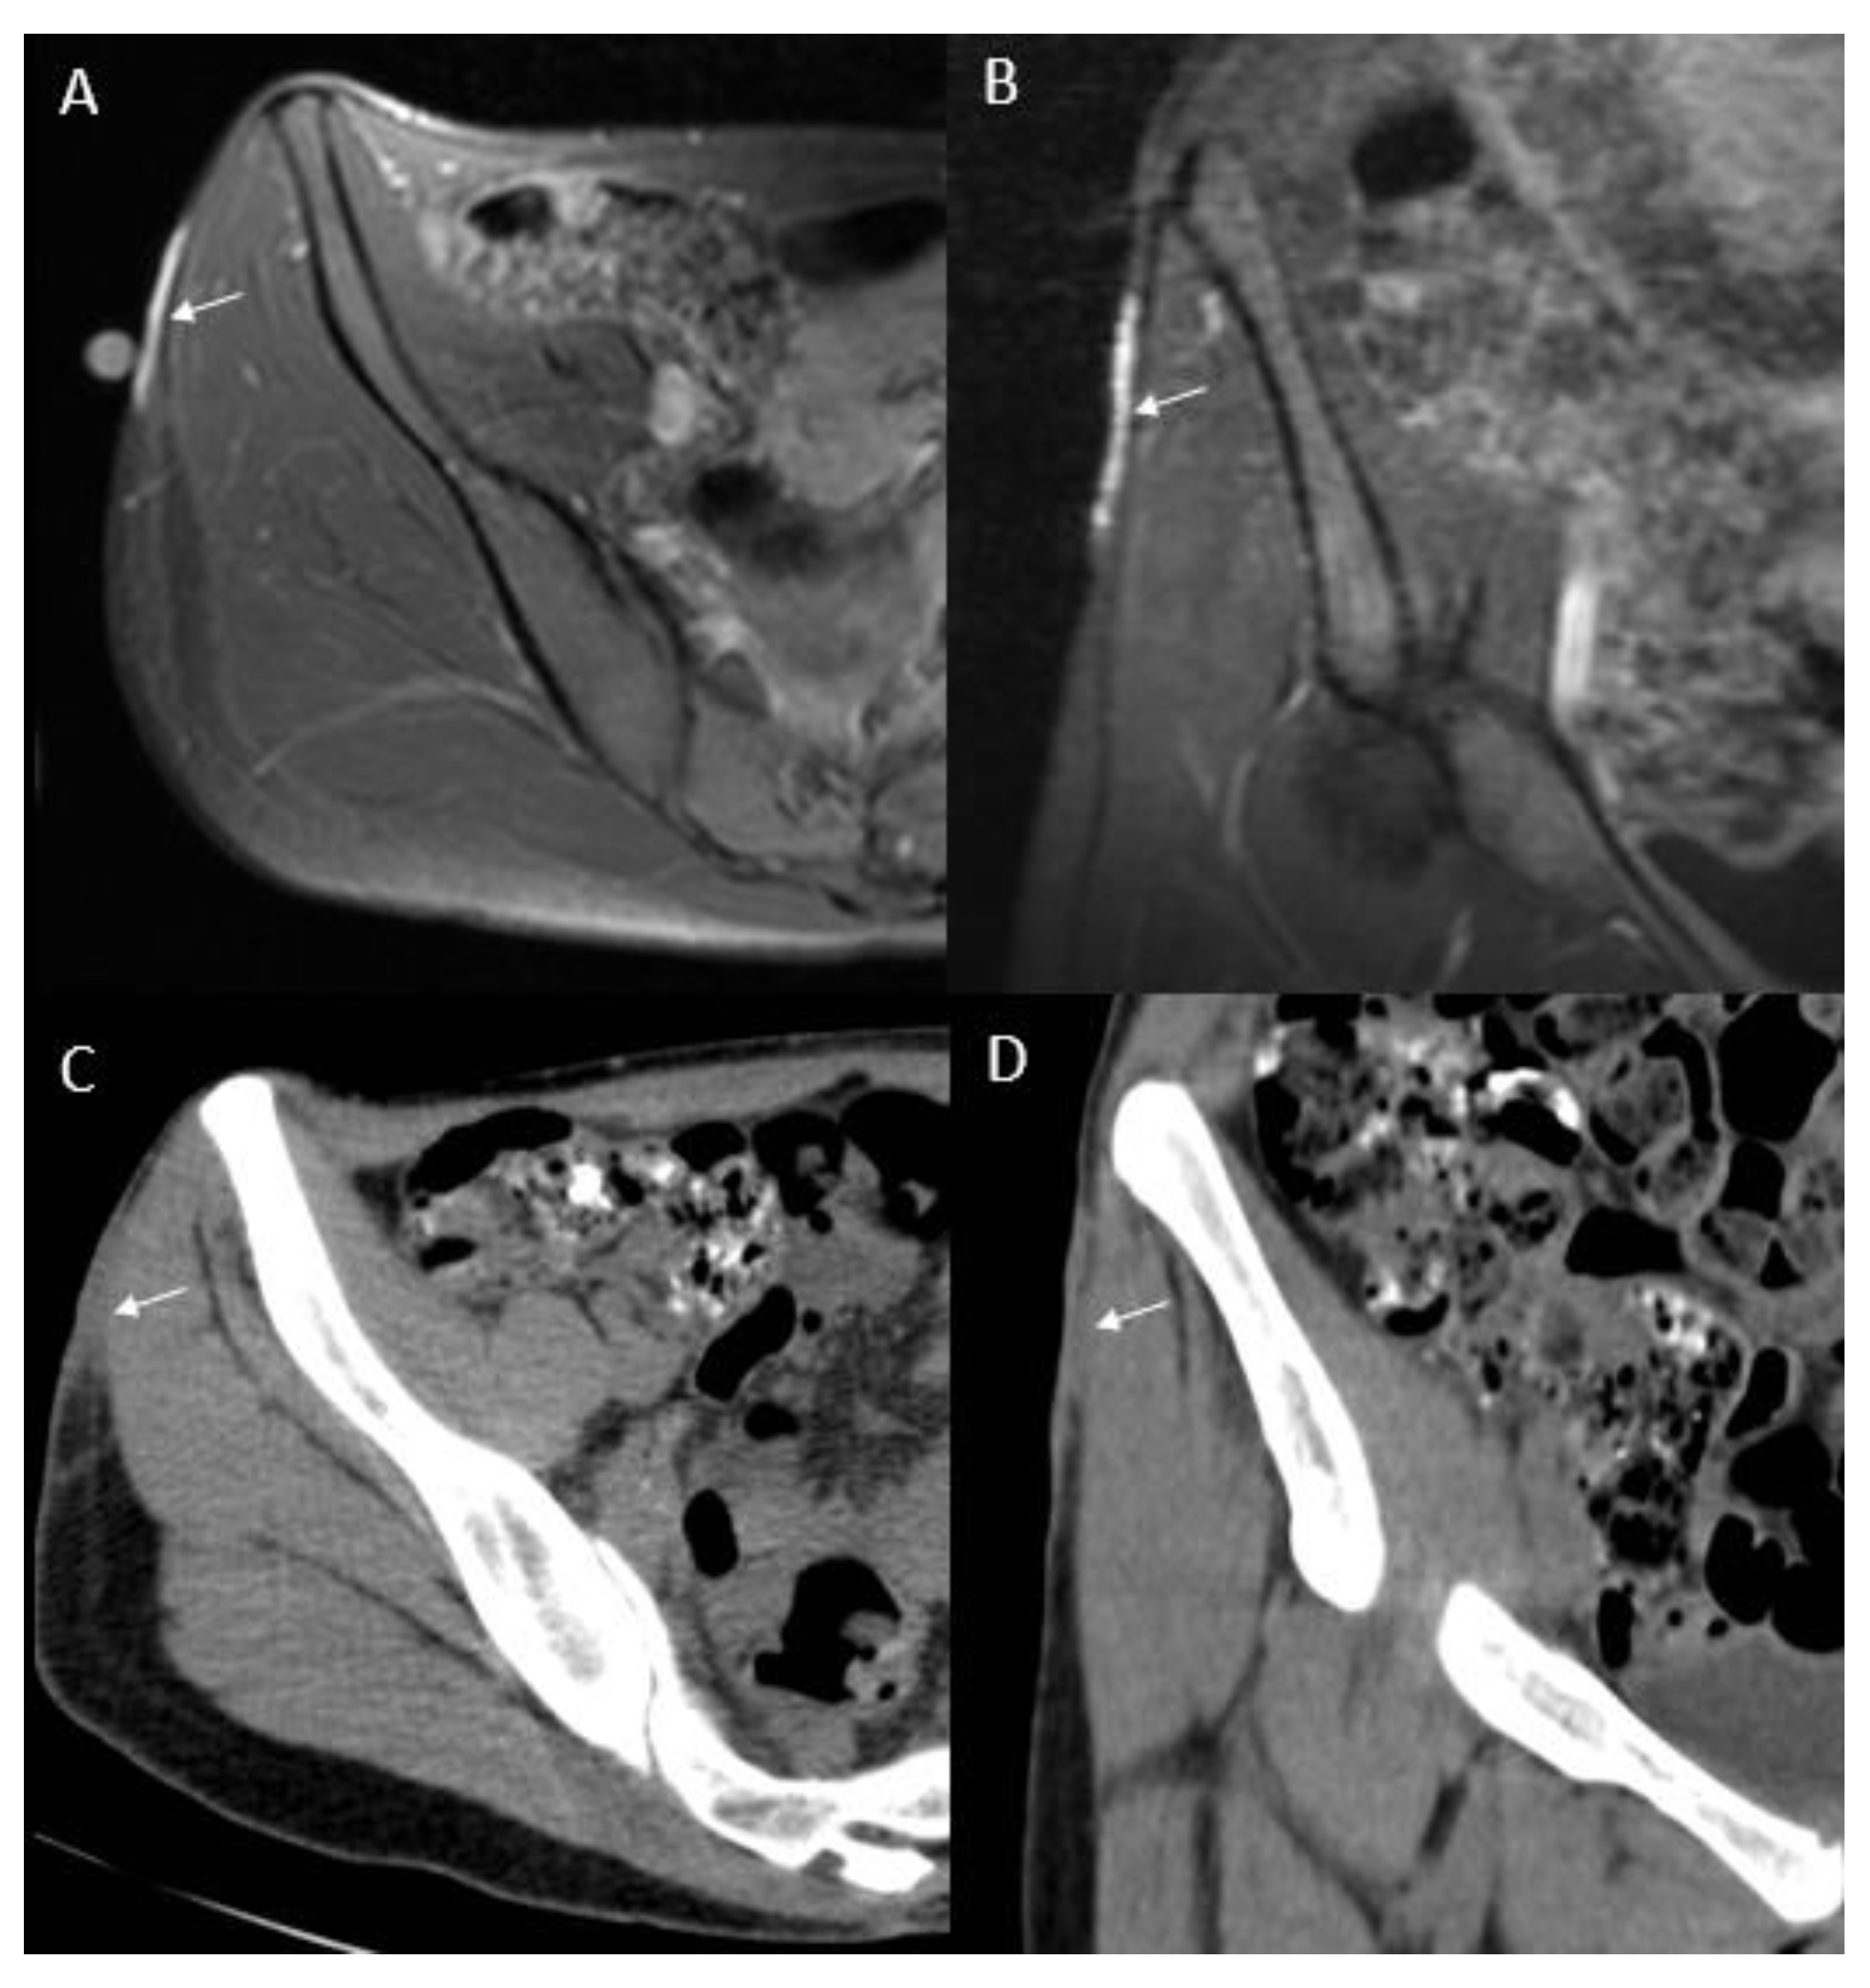

- Thornton, S.L.; Reid, J.; Papay, F.A.; Vidimos, A.T. Childhood dermatofibrosarcoma protuberans: Role of preoperative imaging. J. Am. Acad. Dermatol. 2005, 53, 76–83. [Google Scholar] [CrossRef]

- Riggs, K.; McGuigan, K.L.; Morrison, W.B.; Samie, F.H.; Humphreys, T. Role of magnetic resonance imaging in perioperative assessment of dermatofibrosarcoma protuberans. Dermatol. Surg. 2009, 35, 2036–2041. [Google Scholar] [CrossRef]

- Zhang, L.; Liu, Q.Y.; Cao, Y.; Zhong, J.S.; Zhang, W.D. Dermatofibrosarcoma Protuberans: Computed Tomography and Magnetic Resonance Imaging Findings. Medicine 2015, 94, e1001. [Google Scholar] [CrossRef]

- Torreggiani, W.C.; Al-Ismail, K.; Munk, P.L.; Nicolaou, S.; O’Connell, J.X.; Knowling, M.A. Dermatofibrosarcoma protuberans: MR imaging features. Am. J. Roentgenol. 2002, 178, 989–993. [Google Scholar] [CrossRef]

- Kransdorf, M.J.; Meis-Kindblom, J.M. Dermatofibrosarcoma protuberans: Radiologic appearance. Am. J. Roentgenol. 1994, 163, 391–394. [Google Scholar] [CrossRef] [PubMed]